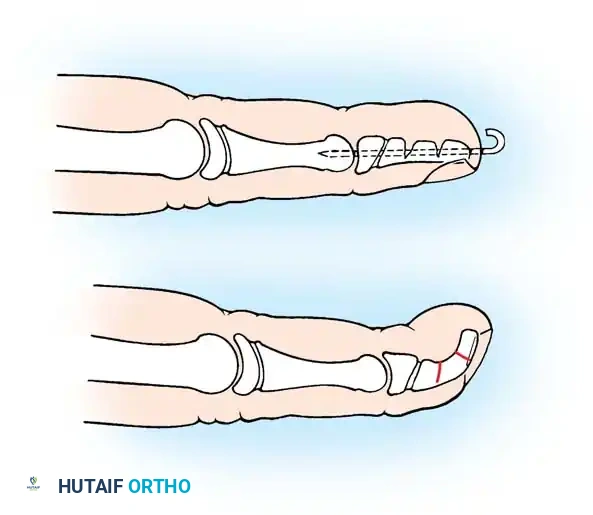

- Pulley Release: Identify the proximal edge of the first annular (A1) pulley. Using a scalpel or fine tenotomy scissors, completely incise the A1 pulley longitudinally under direct vision.

- Verification: Passively flex and extend the IP joint. Ensure the Notta's nodule glides smoothly without impingement.

- Note: Shaving the intratendinous nodule or excising a segment of the A1 pulley is unnecessary and contraindicated, as it risks tendon rupture or bowstringing.

Diagrammatic representation of the A1 pulley release, ensuring the A2 pulley remains intact to prevent bowstringing.

- A1 Pulley Release: Incise the A1 pulley completely from its proximal to distal extent.

- Dynamic Assessment: Passively flex and extend the digit. Inspect the motion of the flexor tendons. If normal gliding of the FDS and FDP is present and triggering has resolved, proceed to closure.

- If an abnormal FDS slip is tethering the FDP, excise one or both slips of the FDS tendon to decompress the sheath.

- Inspect the A3 pulley. If triggering occurs at this level, carefully release the A3 pulley, ensuring the A2 and A4 pulleys remain strictly intact.